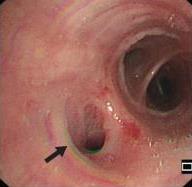

• 侵袭性肺真菌病的支气管镜表现及介入治疗效果

2025, 31(9):81-90. DOI: 10.12235/E20250317

摘要 (112) HTML (56) PDF 6.06 M (77) 评论 (0) 收藏

摘要:目的 探讨侵袭性肺真菌病(IPFD)的支气管镜表现,并评估介入治疗的安全性和疗效。方法 回顾性分析2018年5月12日-2025年5月12日于该院行支气管镜检查的35例IPFD患者的临床资料,观察IPFD的支气管镜表现及介入治疗效果。结果 共收集35例患者临床资料。其中,男22例,女13例,患者年龄(53±14)岁。基础疾病包括:血液系统恶性肿瘤10例,长期应用糖皮质激素者5例,2型糖尿病者4例,肺部恶性肿瘤2例,器官移植1例。胸部CT显示:肺部病变累及单肺叶者19例,累及多肺叶者16例。支气管镜下表现主要为:黏膜充血水肿29例(82.9%)、坏死物堵塞管腔22例(62.9%)、大量黏稠脓性分泌物17例(48.6%)、支气管部分狭窄或闭塞16例(45.7%)、黏膜坏死9例(25.7%)、黏膜出血5例(14.3%)、真菌球3例(8.6%)。其中,32例(91.4%)接受全身性抗真菌治疗,17例(48.6%)接受支气管镜局部两性霉素B灌注治疗,10例(28.6%)采用活检钳钳除病灶,6例(17.1%)采用冷冻探头冻取病灶,4例(11.4%)接受氩气刀治疗。28例(80.0%)临床症状明显改善,肺部影像学病灶缩小或消退;4例(11.4%)病灶稳定;3例(8.6%)未完成治疗。结论 IPFD多见于免疫抑制宿主,支气管镜常表现为:坏死物堵塞管腔、伴脓性分泌物、支气管管腔狭窄和局部黏膜充血水肿或坏死。全身抗真菌药物联合支气管镜下介入治疗,安全性高,且疗效好。